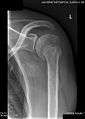

Radiograph showing a bony Bankart lesion with stationary fragment at the inferior glenoid